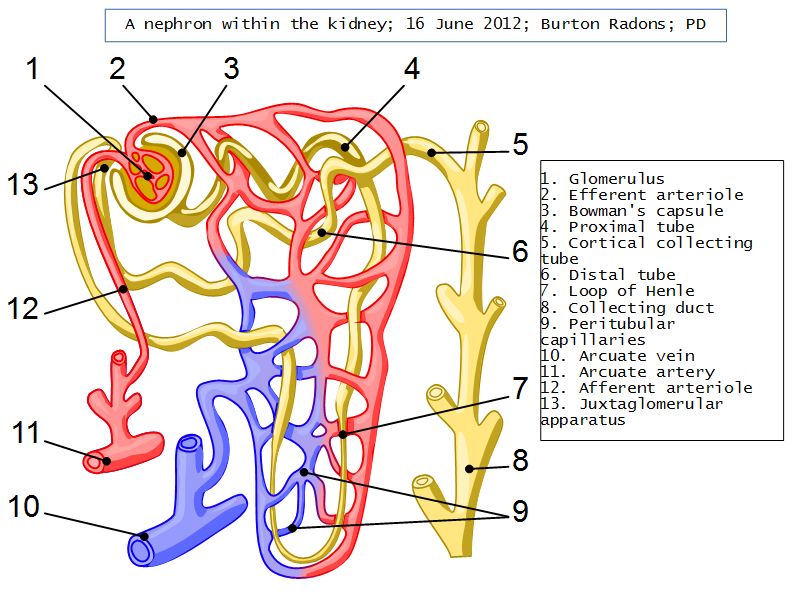

Nephron

- Unit responsible for

- Filtration

- Excretion

- Resorption

- Include

- Kidney tubule

- Glomerulus

- Exclude

- Collecting tubule

Nephron

- Renal corpuscle

- Proximal convoluted segment

- Long loop of Henle

- Descending portion

- Ascending portion

- Distal convoluted segment

Blood flow

- Efferent arteriole

- Smooth muscle in media

- Capillaries

- Fenestrated

- Afferent arteriole

- Smooth muscle in media

Juxtaglomerular complex

Area where distal convoluted tubule return to glomerulus and pass through the notch between the afferent and efferent arterioles. Modification of the wall of the tubule and afferent arteriole and presence of specialised cells in the connective tissue.Modifications

- Distal convoluted tubule

- Macula densa

- Narrow epithelial cells

- Nuclei densely packed

- CT cells

- Laci cells

- Similar to mesangial cells

- Afferent arteriole

- Modified smooth muscle cells

- Juxtaglomerular cells

- Secretory function